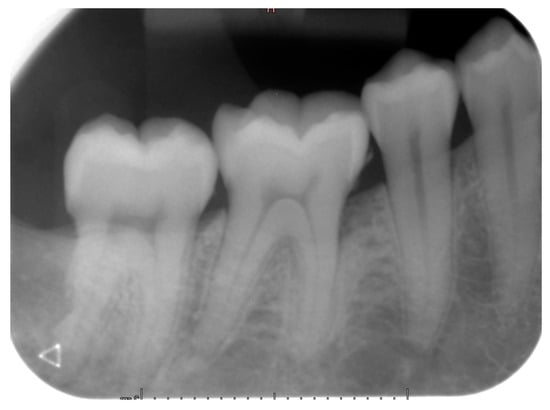

Teeth #18, 28, 38 and 48 were extracted, and the pericoronal lesion in tooth #38 was enucleated in toto under local anesthesia. The diagnosis of DC was confirmed by histopathological examination. The patient was followed-up for two years. At 12 months of control, an intraoral X-ray showed good healing of the enucleation cavity of the follicular cyst (Figure 7). Clinically, tooth #47 remained vital and asymptomatic.

Figure 7.

Intraoral X-ray of case #2 at one-year follow-up exam.